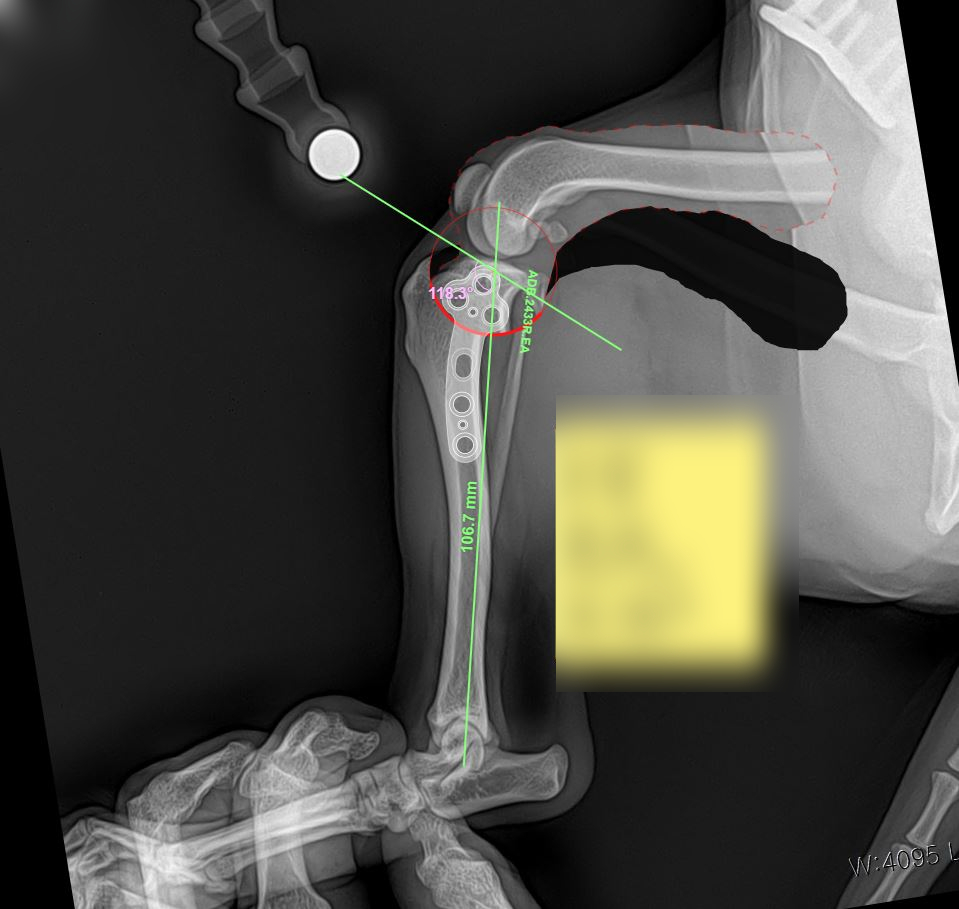

라온동물메디컬센터에서는 동물 정형외과 전용 전문 프로그램을 활용하여 수술 전 정밀 시뮬레이션을 선행한 뒤 진행되었습니다.

개별 환자의 뼈 구조와 각도, 절골 범위를 사전에 계산함으로써 수술 정확도는 물론, 회복 안정성까지 높일 수 있었습니다.

수술 시뮬레이션 사진 / 출처: 라온동물메디컬센터